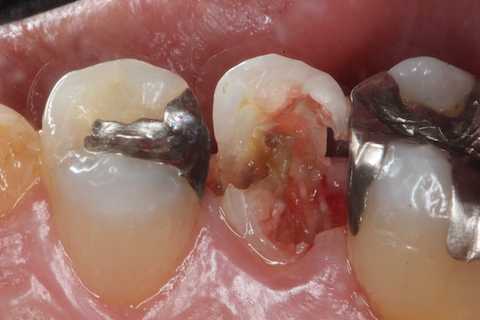

今日の充填治療55(遠心隣接面カリエス) 2023.12.21